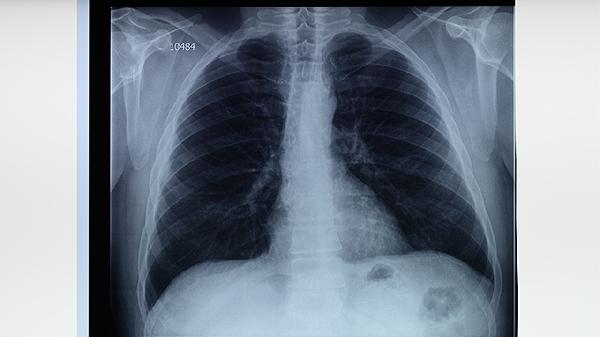

3、定期监测肝功能

治疗初期每2周检测ALT、AST等指标,稳定后每月复查1次。出现食欲减退、皮肤黄染等表现时立即就医,必要时调整用药方案。肝功能异常者可遵医嘱联用异甘草酸镁注射液、还原型谷胱甘肽注射剂等静脉保肝药物,严重时需暂停抗结核治疗。